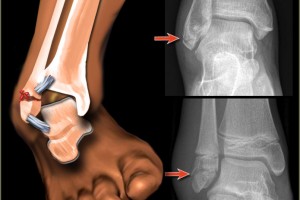

How To Treat An Ankle Fracture

The ankle joint is composed of three bones, which are the tibia, fibula and the talus. Together these bones are joined and they...